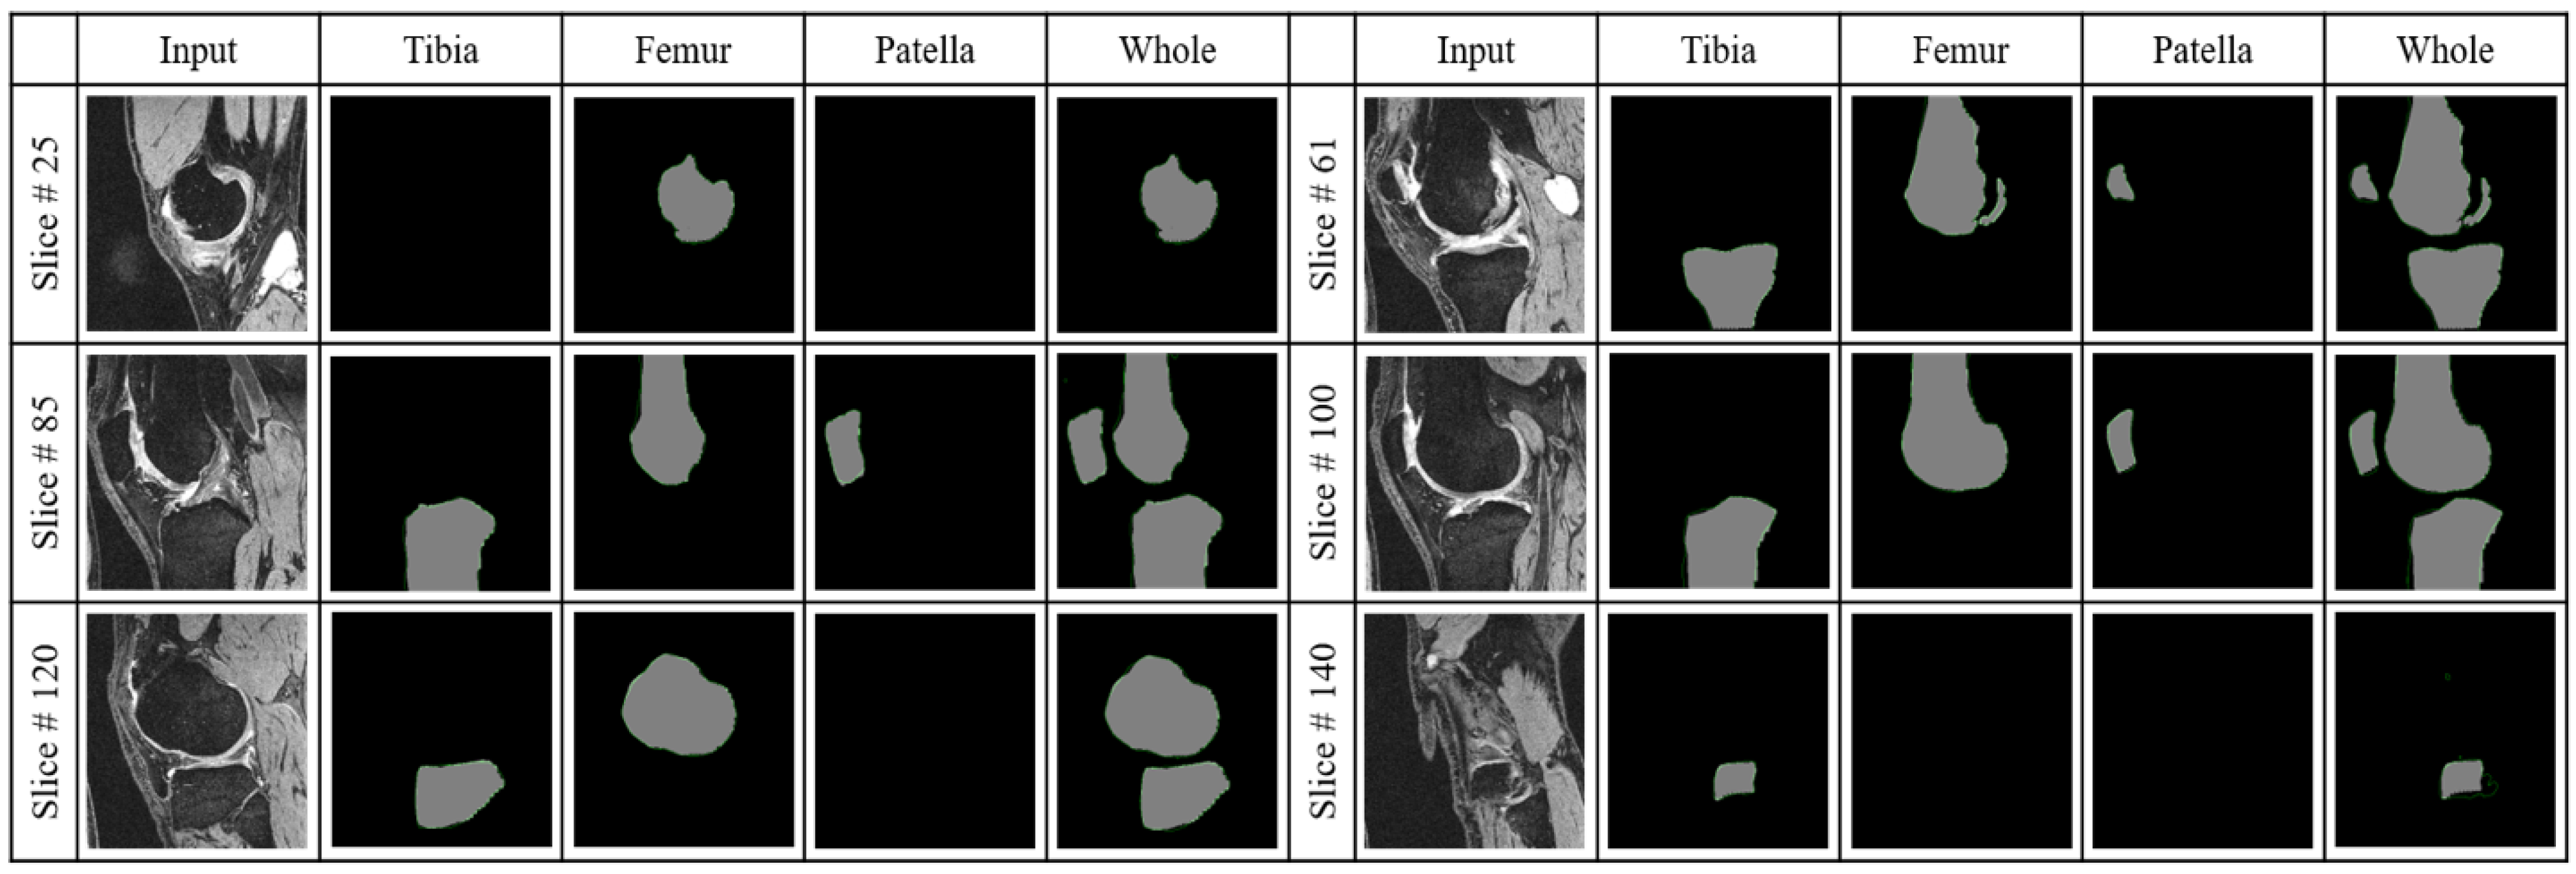

3.2.1. Bone Slice Detection Performance

3.2.2. Segmentation Performance